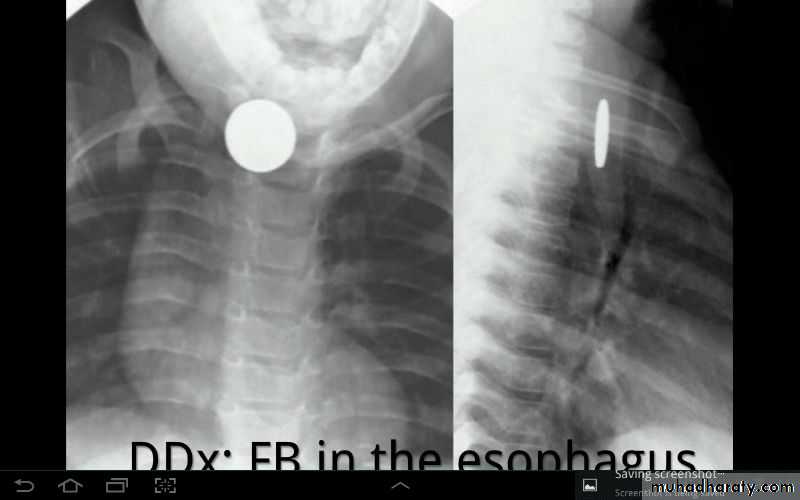

Differential diagnosis?